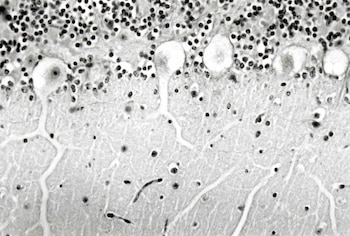

En el año 2000, Robles comenzó a estudiar por primera vez la intoxicación en ovinos. Así, logró describir los síntomas que experimentan los animales y que son de tipo nervioso: perdían el equilibrio, quedaban ciegos, se tropezaban con objetos y finalmente morían. "Pudimos detectar el origen de toda esa sintomatología ya que encontramos lesiones en el sistema nervioso central que afectaba neuronas de distintos núcleos del tallo cerebral y en neuronas del cerebelo que están directamente relacionadas con el equilibrio de los animales. Así logramos esclarecer el origen de los síntomas clínicos de la enfermedad", explicó el investigador.